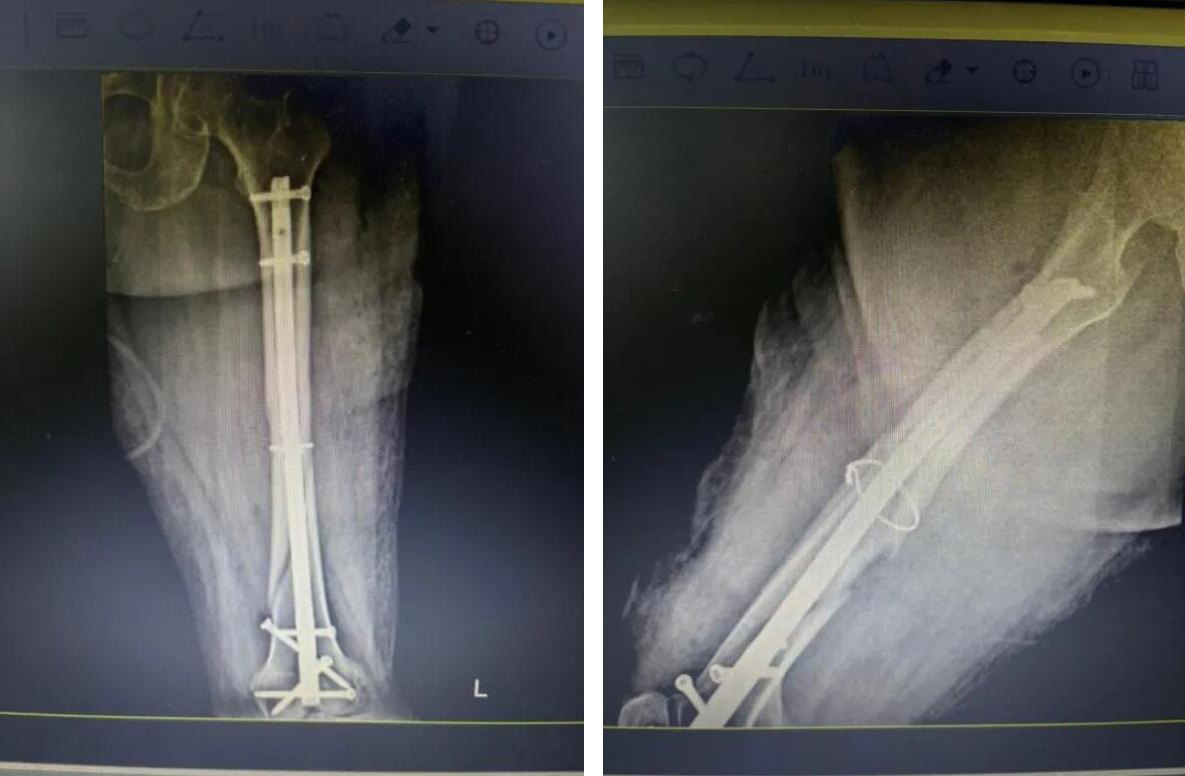

经过充分准备,医疗团队决定为俞奶奶实施 “闭合复位微创内固定术”。

与传统开放手术不同,医生不在骨折处做长切口,而是通过几个仅1-2厘米的“钥匙孔”小切口,在C型臂X光机的精准导航下,将骨折断端巧妙地对合复位,然后植入髓内钉进行坚固固定。

手术历时约一小时,过程非常顺利。术中出血量极少,最大程度减少了对患者生理机能的干扰。